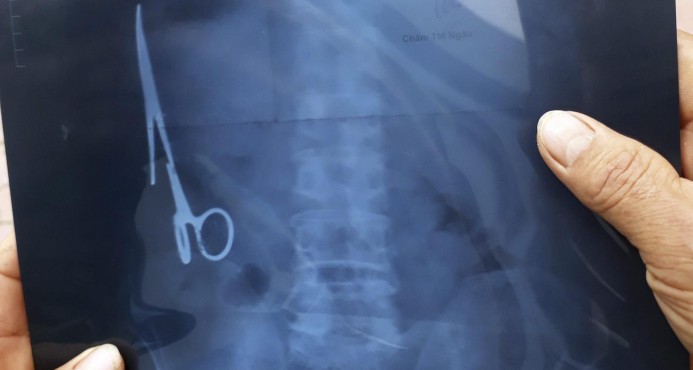

Retiran tijeras a vietnamita que llevaba 18 años en su estómago

Bangkok, (EFE).- Un vietnamita ha vivido 18 años con unas tijeras que los médicos se olvidaron en su estómago y de cuya presencia nadie se había dado cuenta hasta el mes pasado, cuando sufrió un accidente de tráfico y le hicieron una radiografía.

La intervención quirúrgica para retirar el instrumento médico de 15 centímetros de largo se realizó el sábado pasado en un hospital de la provincia de Thai Nguyen, en el norte de Vietnam, y duró unas tres horas.

Las tijeras se encontraban oxidadas, en la parte izquierda del estómago, según los doctores que el intervinieron citados por el medio vietnamita Tuoi Tre.

El paciente, un hombre de 54 años, nunca había sentido molestias por la presencia de las tijeras que se olvidaron en su estómago en junio de 1988, cuando le intervinieron en el Hospital General Bac Kan por otro accidente de tráfico.